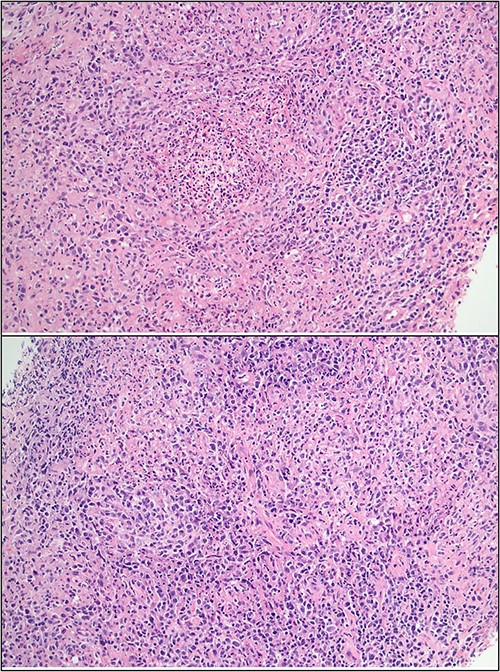

Ultrasound of the right axillary mass indicated a single enlarged lymph node measuring 26 × 25 × 40 mm (Fig. 1). Following discussion with haematology and infectious disease specialists, a nodal core biopsy was performed. This identified an atypical lymphoid infiltrate primarily characterized by CD138+/IRF4+ plasma cell clusters, interspersed by CD3+/CD5+ T cells and scattered necrotic foci (Fig. 2). As this was a core biopsy, nodal architecture was not appreciable. There was mild positivity for plasma cells on EBV-encoded small RNA in situ hybridization (EBER-ISH), consistent with the patient’s positive EBV PCR status. Bacterial and fungal specimen culture was negative, including for Mycobacterium tuberculosis, and flow cytometry did not detect any monotypic B cells or aberrant T cells.

Core biopsy histology showing lymphoid infiltrate with foci of suppuration and dense plasma infiltrate.